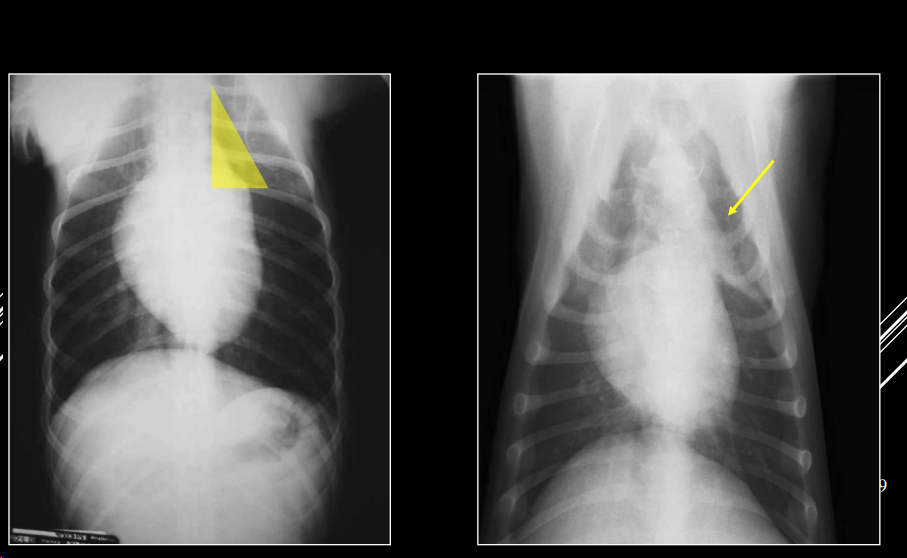

- Alteraciones de posición del mediastino (Desplazamiento mediastino VD)

- Alteraciones en la visualización de estructuras mediastinicas (Neumomediastino LL)

- Alteraciones de la anchura del mediastino (Derrame mediastinico o masa mediastinica VD)

1. Desplazamientos

- Artefacto (rotación): desplazamiento no real. Si se ve el esternon está mal

- Por enfermedad pleural (neumotórax): desplazamiento no real.

- Masa mediastínica: desplazamiento real.

2. Neumomediastino

- Aire en mediastino craneoventral.

- Mayor visualización de estructuras mediastínicas en vez de ver efecto masa en la zona mediastinica craneal, presencia de negros en la zona craneal y mejor visualización de vasos y traquea.

- Enfisemas subcutaneos suelen ocurrir, quedando aire entre las fascias y subcutaneo. Incluso puede pasar a la cavidad abdominal.

- “Tracheal stripe sign”.

- Puede coexistir con enfisema subcutáneo, neumotórax o neumoretroperitoneo.

- Generalmente por rotura traqueal (A veces por rotura esofágica)

- Es la unica forma de diagnosticar un neumodiastino.